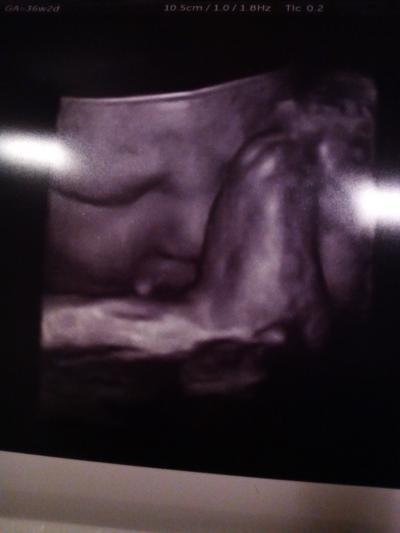

Hallo ihr Lieben, nachdem ich eine Nacht im KH zur Beobachtung verbringen musste wegen meinem Blutdruck und ich Topwerte hatte, sollte ich eigentlich gestern Nachmittag entlassen werden. Gab da wohl nur ein Problem, es hat wohl niemand dran gedacht, das gestern ein sehr schönes Datum war und demzufolge kamen so viele Frauen zum entbinden, das meine Entlassung in weite Ferne rückte. Habe mir die Zeit dennoch gut vertrieben in dem ich direkt zwei Muttis aus meinem GVK getroffen hatte. Die eine hatte in der Nacht ihr Baby bekommen und die andere kämpfte noch fleissig mit ihren Wehen. Hoffe sie ist gestern noch Mami geworden. 18:30 Uhr dann endlich durfte ich in den US, wo meine Hummel nochmal auf Herz und Nieren geschallt wurde und auch vermessen. Wobei die Ärztin sich wieder wunderte das der Entbindungstermin nicht korrigiert wurde. Stolze 50 cm und 3331 Gramm kamen heraus und die Ärztin und ich hatten dann riesigen Spass beim 3D US. Sie sagte gleich ich könne die kleine gleich zur Leichtathletik anmelden. Möchte euch den Grund dafür nicht vorenthalten und euch ein Bildchen zeigen. Muss dazu sagen, das ich mich total verliebt habe, in meine kleine Hummel und nun noch hibbeliger bin und sie endlich in den Armen halten möchte.

Bild zu wieder zu Hause - Forum für März - Mamis

Süß, die übt ja ganz schön für draußen, da machen sie sowas auch oft später und halten die Beine dann noch fest.

Hihihi. Spontan musst ich an Turmspringen denken. 2 1/2facher gestreckter Salto....und perfekt eingetaucht

Betet sie mit den Füßen??? Oh man....die ist ja voll süß!!!

Na erst hatte sie die Hände über den Kopf zusammengeschlagen. Dachte bestimmt was machen die denn da? Und dann zeigte sie eben was sie kann. Deshalb liegt sie bestimmt in BEL, weil mit Köpfchen tief im Becken geht es ja nicht mehr.